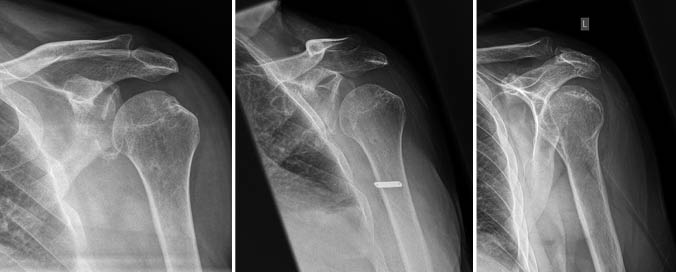

Zur Zusammenhangsbegutachtung steht der Fall eines Versicherten, welcher eine arbeitsunfallbedingte persistierende hintere Schulterinstabilität links bei berufsgenossenschaftlich anerkannter Vorerkrankung am Schultergelenk erlitt. Berichtet wird über die medizinische Behandlung und den unfallbedingten Verschlimmerungsanteil bei Vorerkrankung am Schultergelenk. Nach Implantation einer inversen Schulterendoprothese links resultiert bei weiterem komplikationslosen postoperativen Rehabilitationsverlauf keine messbare MdE aus dem zu beurteilenden Unfall.